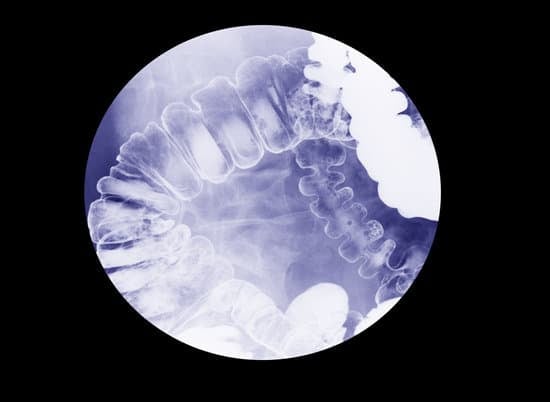

대장 조영술 (Barium Enema)

대장 조영술은 바륨이라는 조영제를 사용하여 대장과 직장의 상태를 X-레이로 확인하는 검사입니다.

이 검사는 대장의 구조적 문제나 질병을 진단하는 데 사용되며, 대장 내시경 검사를 대신할 수 있는 방법으로 대장 폴립, 종양, 염증성 질환, 게실 등의 이상을 발견하는 데 도움이 됩니다.

검사를 시작하면 바륨이라는 흰색의 조영제를 직장으로 주입합니다. 바륨은 대장을 코팅하여 X-레이 촬영 시 대장의 형태와 내부 구조를 더 선명하게 보여줍니다.

바륨을 주입한 후, 공기를 주입하여 대장을 팽창시킵니다. 대장을 팽창시켜 대장 내벽을 더 명확하게 관찰할 수 있게 됩니다. 이 과정은 이중 조영술이라고 하며, 작은 이상도 쉽게 발견할 수 있도록 도와줍니다.

다양한 각도에서 X-레이 촬영을 진행합니다. 바륨이 대장 내벽을 코팅하고 공기가 대장을 확장시킴으로써, 대장의 구조적 이상을 선명하게 확인할 수 있습니다.